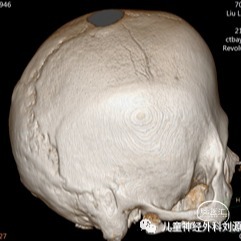

矢状缝早闭是最常见的颅缝早闭,根据颅骨生长规律,矢状方向上骨缝闭合

图片尺寸400x403

性,特别指出的是即使已经30岁,依然可以看到清晰的额缝,即使其已闭合

影像,经过全外显子基因检测证实为muenke综合征,其特点为冠状缝闭合